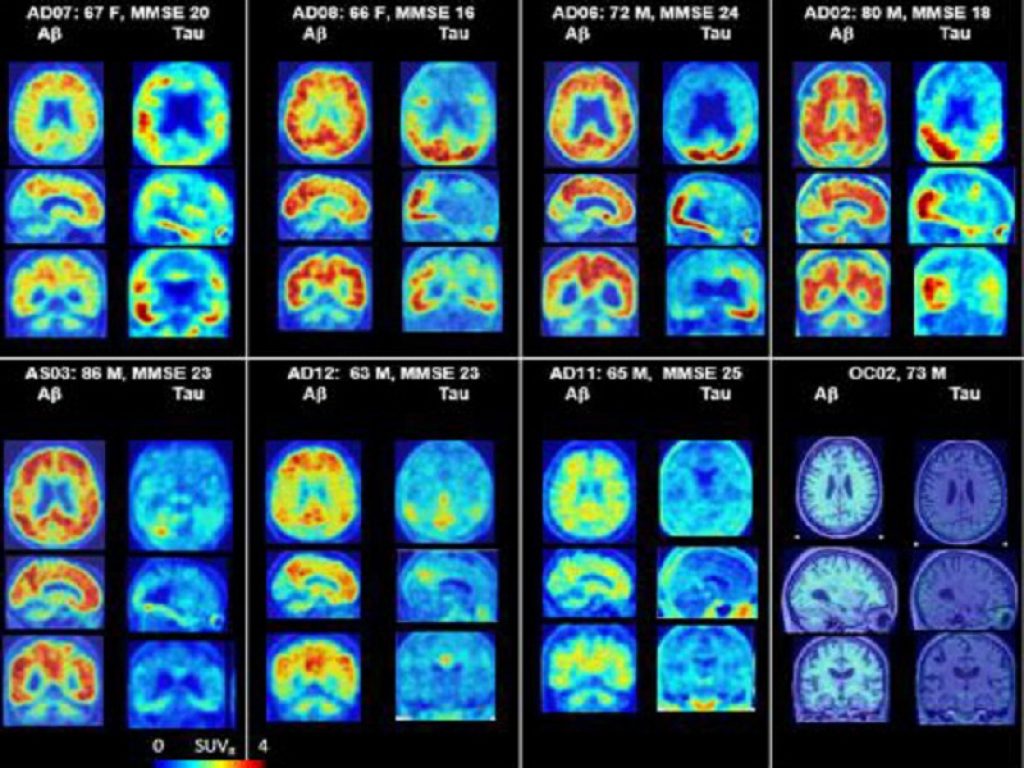

Nel caso dell’Alzheimer, l’algoritmo ha analizzato l’esito di semplici test neuropsicologici volti a stimare la probabilità di insorgenza della patologia a seconda del sesso sulla base di parametri “predittori” come la memoria, l’orientamento, l’attenzione e il linguaggio (MMSE); la memoria verbale a breve termine (AVTOT); e la memoria episodica a lungo termine (LDELTOTAL) “Il sistema di machine learning che abbiamo sviluppato mostra come MMSE è un predittore più efficace dell’Alzheimer nelle donne, mentre negli uomini è essenziale per il monitoraggio a lungo termine. LDELTOTAL è più predittivo nelle donne per l’insorgenza della malattia, mentre AVTOT è più rilevante negli uomini. Inoltre, il livello di istruzione incide in modo diverso sul rischio di Alzheimer, con le donne che presentano un rischio maggiore”, prosegue il ricercatore.